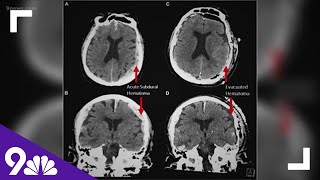

The most important lesson from 83,000 brain scans | Daniel Amen | TEDxOrangeCoast Dying Man's Brain Scan Suggests Life Could Flash Before Your Eyes | NBC4 Washington

The most important lesson from 83,000 brain scans | Daniel Amen | TEDxOrangeCoast Dying Man's Brain Scan Suggests Life Could Flash Before Your Eyes | NBC4 Washington